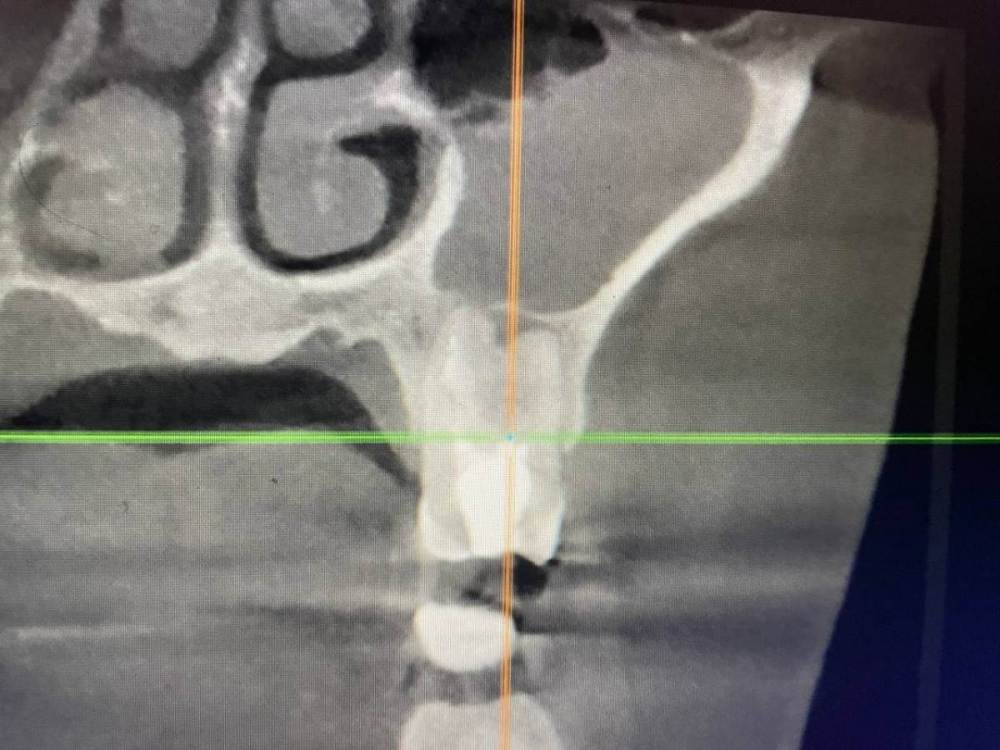

1586Doc Опубликовано 8 февраля, 2020 Поделиться Опубликовано 8 февраля, 2020 5 месяцев назад обратилась пациентка с симптоматикой периодонтита. Оценили, попробовали. Пломбировка вертикалка. 5 месяцев и контроль, боли нет, подвижности тоже. 2 Ссылка на комментарий

1586Doc Опубликовано 10 февраля, 2020 Автор Поделиться Опубликовано 10 февраля, 2020 (изменено) А где контроль на сегодня? При таком качестве снимков оценить будет тяжело.первые 2 фото снимки 9 месяц назад, до ревизии Изменено 10 февраля, 2020 пользователем 1586Doc Ссылка на комментарий

1586Doc Опубликовано 17 января, 2021 Автор Поделиться Опубликовано 17 января, 2021 еще один кейс.Утолщение слизистой гайморовой, хронический процесс на 25.26 зубахконтроль клкт через 8 месяцев Ссылка на комментарий

1586Doc Опубликовано 17 января, 2021 Автор Поделиться Опубликовано 17 января, 2021 первые 3 фото, ретрит 14 зуб4.5 фото 45 зуб. 4 Ссылка на комментарий